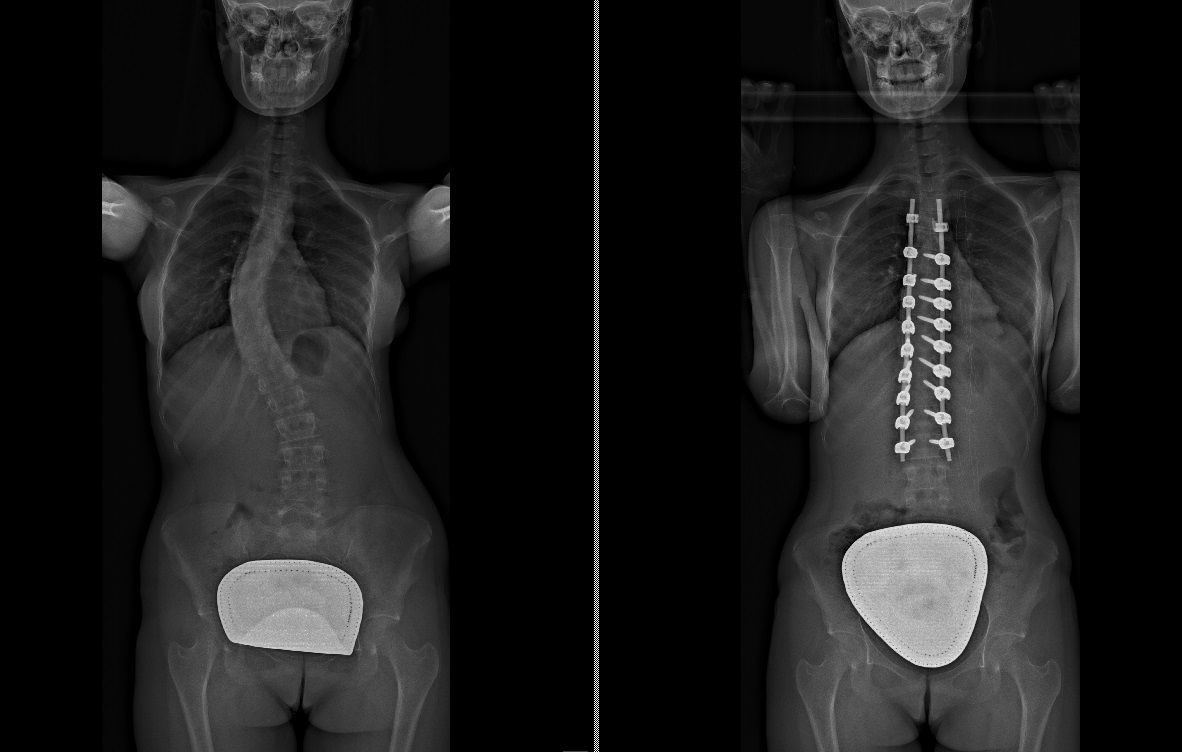

Laureato in Medicina e Chirurgia presso l'Università degli Studi di Napoli Federico II nel 2011, Specializzato in Ortopedia e Traumatologia presso la stessa Università nel 2017. Da subito ho dedicato i miei studi all'ambito della chirurgia vertebrale e della neurochirurgia. Infatti ho frequentato per 9 mesi tra il 2015 ed il 2016 i reparti di Neurochirurgia dell'IRCCS Neuromed di Pozzilli (IS) per apprendere le tecniche di trattamento delle Patologie della Colonna Vertebrale. Da allora il mio principale interesse è rivolto al trattamento conservativo e, dove necessario, chirurgico delle deformità della colonna vertebrale, sia dell’età dell’accrescimento che degenerative dell’adulto: scoliosi, dorso curvo, spondilolisi, spondilolistesi. Ulteriori campi di interesse sono il trattamento di lombalgia e lombosciatalgia, ernia del disco, stenosi del canale vertebrale, fratture vertebrali traumatiche o da osteoporosi (vertebroplastica), terapia del dolore osteoarticolare mediante tecniche mininvasive (radiofrequenze). Dal 2017 sono Consulente presso IRCCS Neuromed di Pozzilli (IS) con incarico di Responsabile del Centro per la Diagnosi e Cura delle Deformità Vertebrali e Scoliosi, dove svolgo la mia attività chirurgica in regime di convenzione. Svolgo la mia attività chirurgica in regime di solvenza e di convenzione assicurati presso la Clinica Ruesch di Napoli. Continuo costantemente la mia formazione con esperienze di perfezionamento nazionali ed internazionali. Infine, dal 2020 sono Docente per l'Università degli Studi di Roma "La Sapienza".

• Chirurgia vertebrale

Foto e video